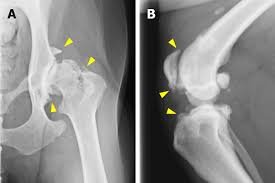

hip dysplasia dr hart

• hip dysplasia

hip arthritis dog

Hips

Hip arthritis is very common in older dogs and may cause trouble rising, stiffness, or a swaying rear gait.

Knees

knee arthritis dog

Dogs with knee arthritis may limp, hold up a leg, or move more stiffly after activity. Previous cruciate injuries often lead to arthritis.